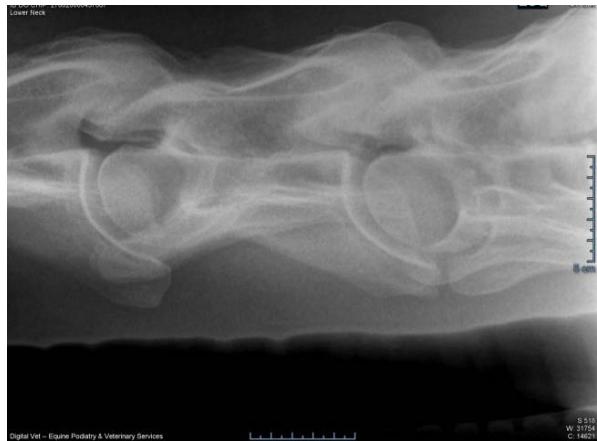

According to the images in figures 1 and 2, both in the group with congenital problems and in the group without congenital problems, there is a clear irregularity of the tracheal cartilaginous rings, which does not represent any problem of a functional nature, as the important thing is that there is no resistance to the air passed through the trachea both during exhalation and inspiration and that this finding represents only an anatomical confirmation, a fact that is very little reported whether in anatomy textbooks or findings in this scientific essay.

There is indeed a change in the dorsal region of the tracheal rings seen in the radiographs of GI (fig, 3) where there is the presence of a "ridge", seen in all animals in this group, not occurring in the GII group.

Fig. 1, 2: There is Irregularity of the Tracheal Rings (Blue Arrow)

Fig. 3: The Tracheal Rings Seen in the Radiographs of GI where there is the Presence of A " Ridge"(Blue Arrows)

The simple lateral projection radiographs initially showed that the tracheal rings in all horses from both groups are of different sizes and shapes, regardless of whether the animal has or does not have a neurological problem located in the cervical region. Irregularities in the cartilaginous rings ("ridge"), were present in all horses with congenital cervical malformations, that is, we found this lesion in all horses with congenital cervical problems in this study, but we suggest further studies using better investigation techniques.